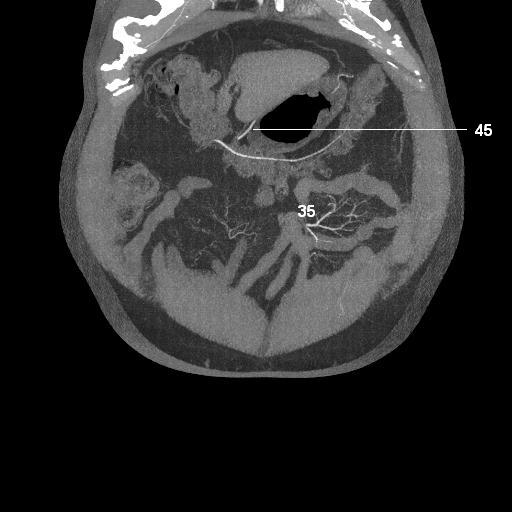

35. jejunal arteries

45. right gastroepiploic artery